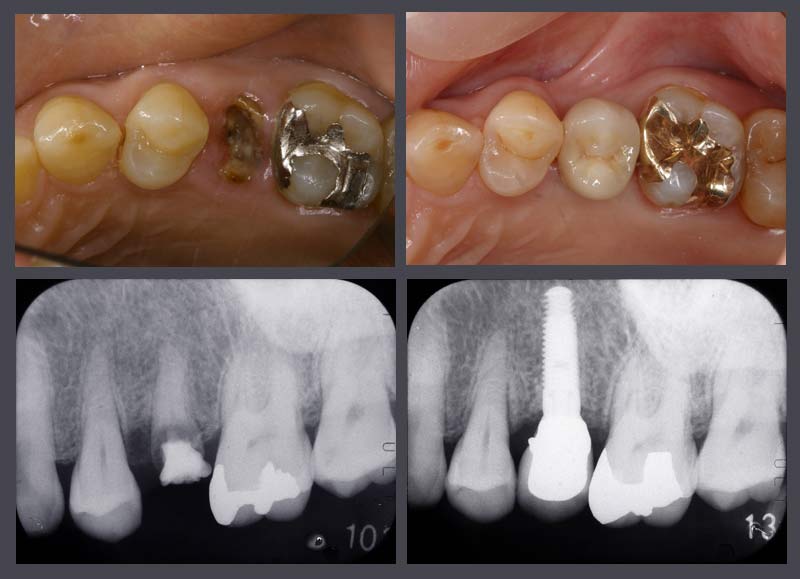

インプラントの手術経験も300ケースを超えました。お口の中の状態を慎重に診断し無理のない安全なインプラント治療を行っています。患者さんにお聞きしていると世間でのインプラントの評価は二分されているようです。評判が悪くなるのは無理なケースに乱暴な術式でインプラントをおこなったケースのようです。インプラントにも適応症がありすべての患者さんにできるものでもありません。須貝歯科医院では安全で確実にできるインプラントを患者さんに勧めています。難しい症例は鶴見大学に依頼しCTを撮影してもらいインプラント科で処置を行ってもらっています。

保存不可能な歯根を抜いてその日のうちにインプラントを入れたケースです。従来であれば前後の歯を削ってブリッジにしなければならないケースですがイン プラントを使えば前後の歯にダメージを与えることなく歯を入れることができます。